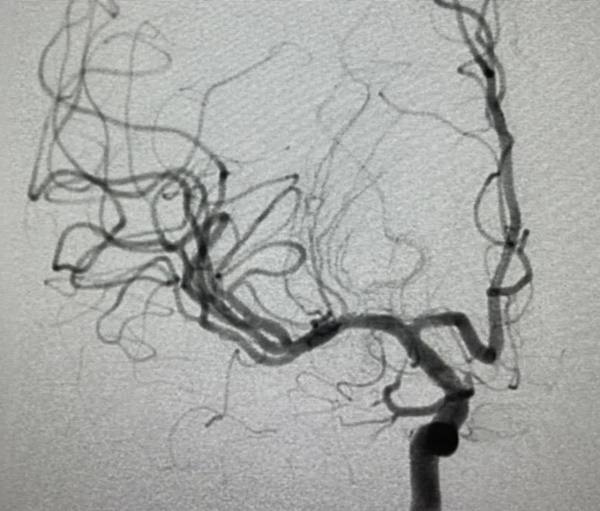

Bác sĩ Lưu Phương Kỳ đã dẫn đầu kíp trực, tiến hành chụp mạch não và phẫu thuật lấy huyết khối nội mạch cho Tiểu Vương. Sau ca phẫu thuật, Tiểu Vương đã lấy lại được khả năng nói lưu loát và chi trái có thể tự do nâng lên.

Sau khi phẫu thuật, lưu lượng máu của động mạch não đã được phục hồi

Sau khi phẫu thuật, bàn tay trái vốn dĩ đã bất động của Tiểu Vương có thể giơ lên ngay lập tức